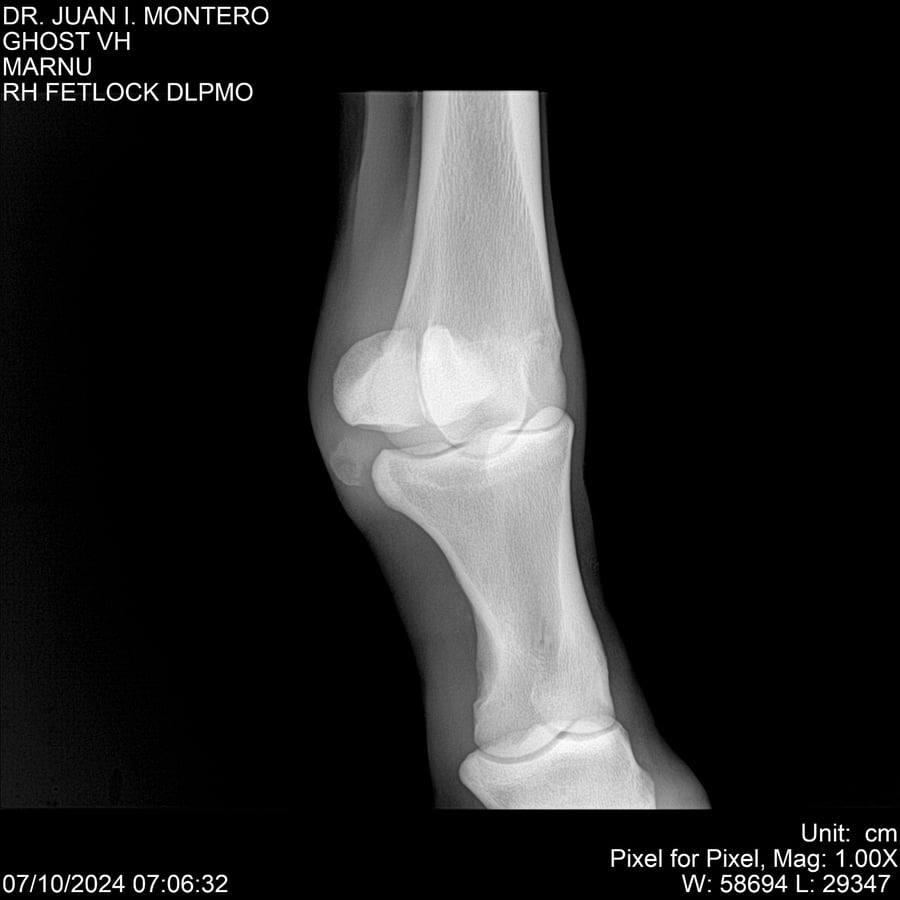

LOTE 15, GHOST VH 🔥 🔥 🔥 Lote Anterior Volver al remate Lote Siguiente Ficha Contacto Montevideo - Ficha del Lote Identificador: #282525 Categoría: Yeguarizos Montevideo - 69 Visualizaciones ClicData Contacto Empresa: Abelenda N. R., Walter Hugo Nombre*: Teléfono* : E-mail* : Mensaje Enviar Registrese gratis Este contenido Exclusivo está disponible sólo para usuarios registrados Ingresar